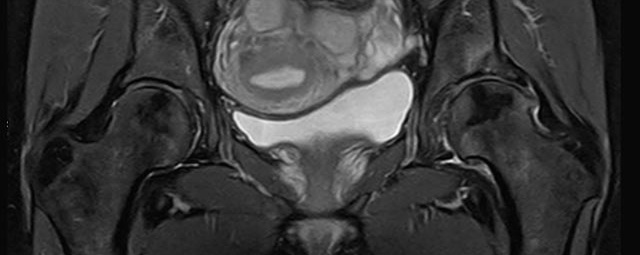

- Urogenitalorgane

- Tumordiagnostik z.B. im Bereich der Ovarien, des Uterus, der Prostata oder Harnblase

- dynamische MR-Analyse bei Beckenbodeninsuffizienz

- Darstellung bzw. Kontrolle im Verlauf bei perianalen Fisteln und Abszessen

- Verlaufskontrolle des Lokalbefundes nach Rektumentfernung bei Karzinom